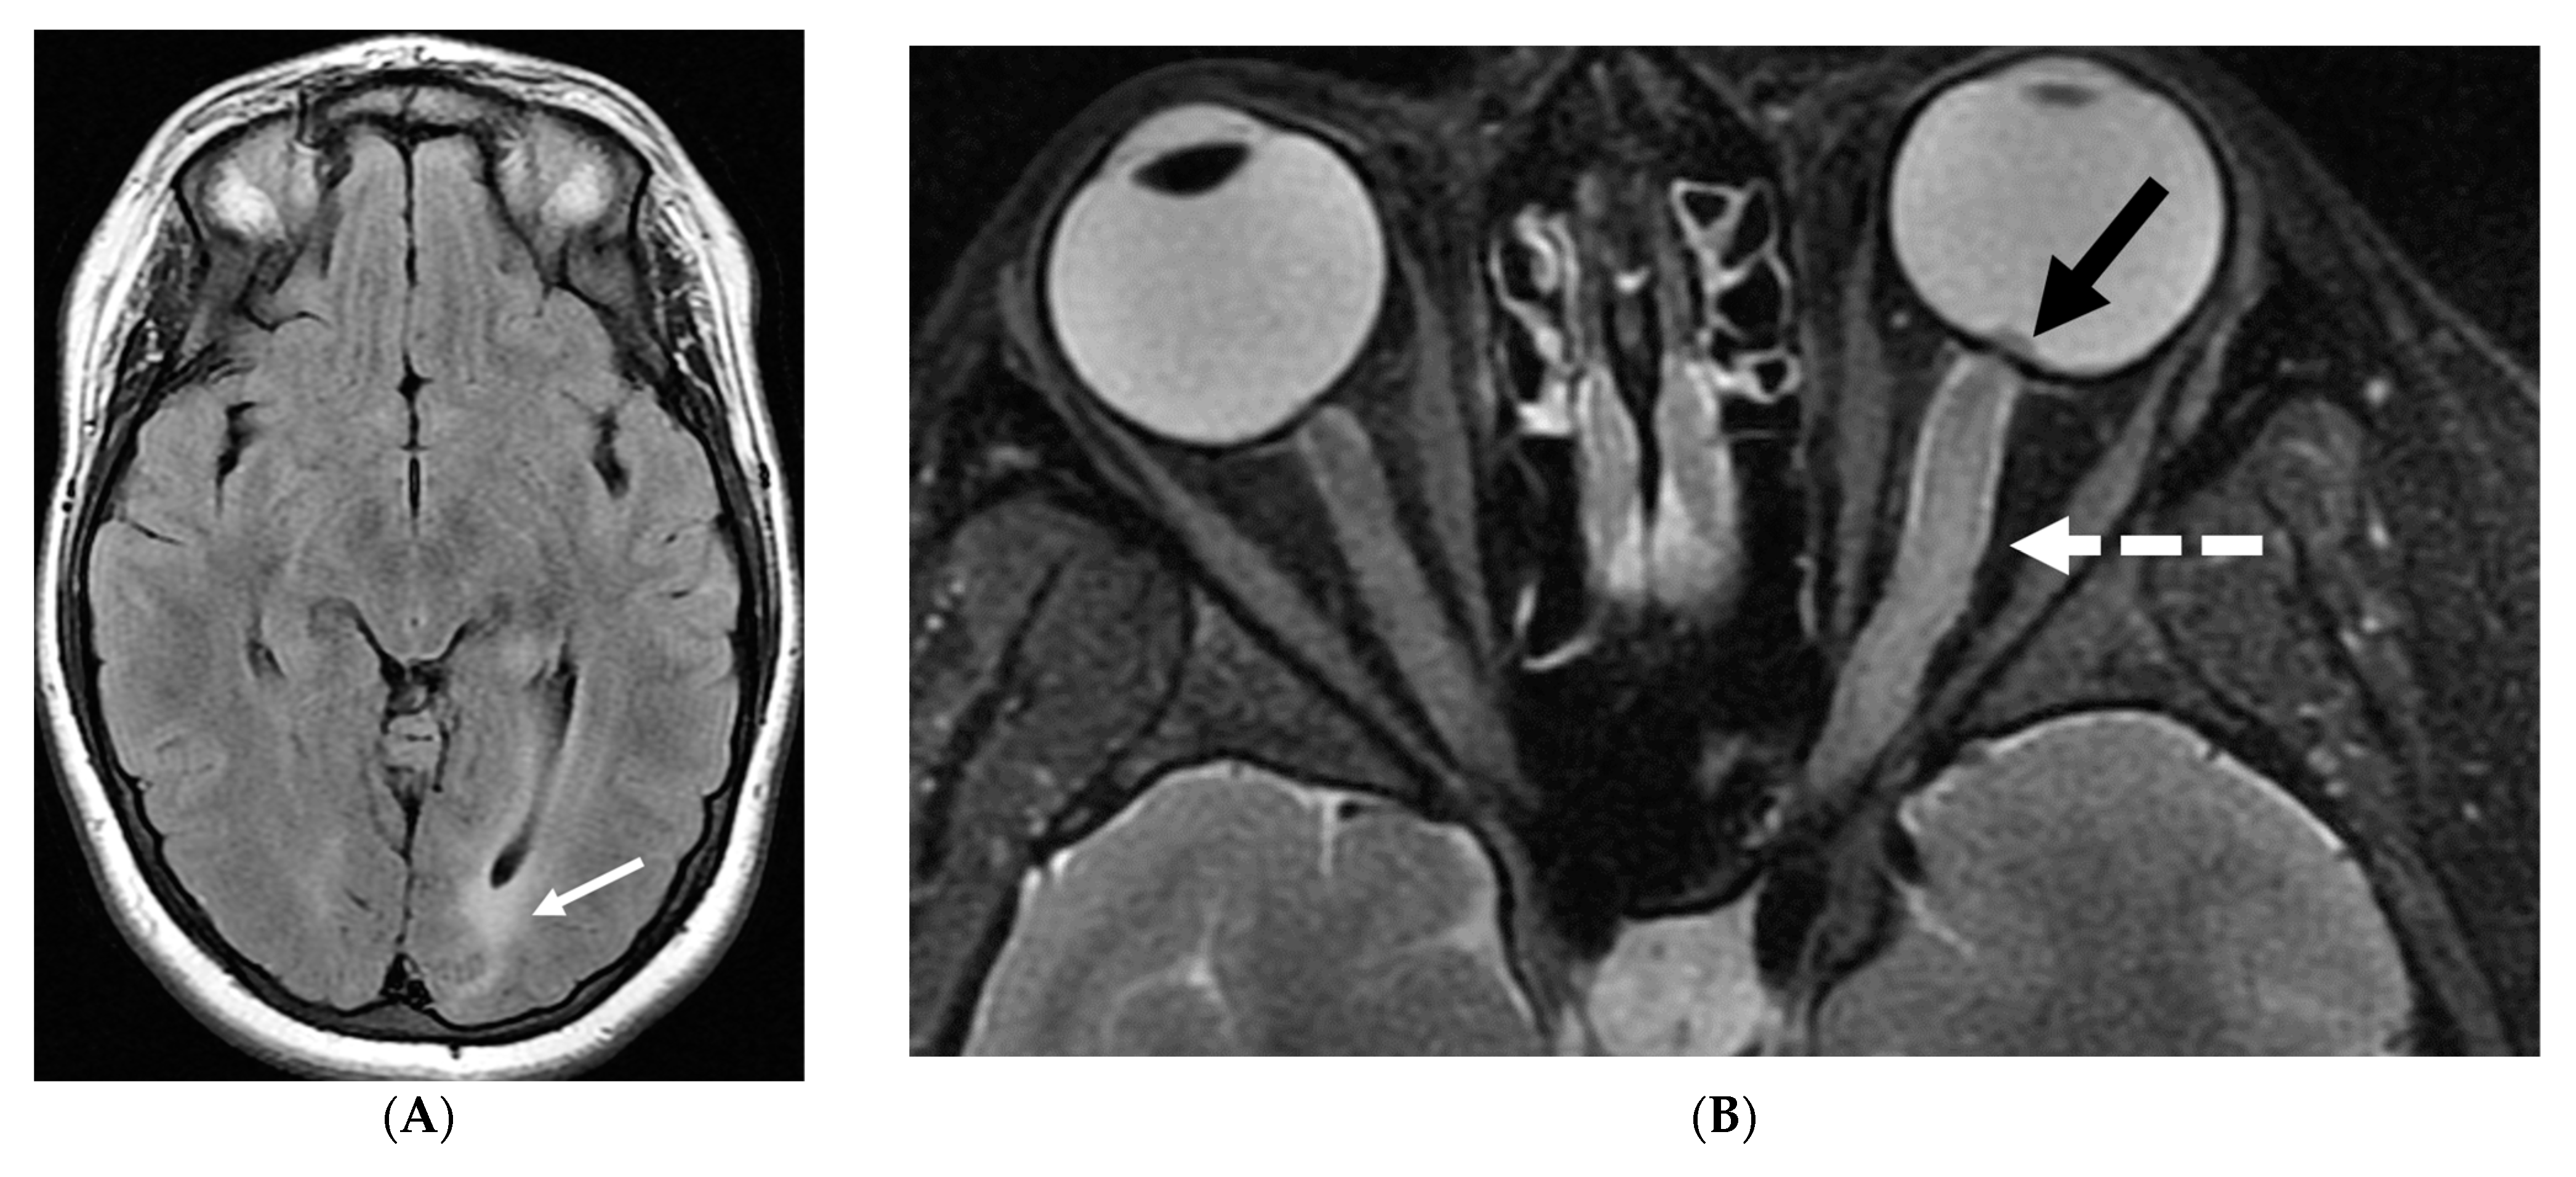

5.3. Anti-Myelin Oligodendrocyte Glycoprotein (MOG) Demyelination

Anti-MOG antibody associated demyelination (MOGAD) frequently presents as Acute Disseminated Encephalomyelitis (ADEM) in children and opticospinal involvement in young adults [105]. Bilateral but asymmetric T2 hyperintense lesions occur in thalamus, pons and cerebellar peduncles are common in children [106]. Optic nerve involvement typically presents as a long segment with anterior predominance, in contrast to the posterior predominance seen in Neuromyelitis Optica Spectrum Disorders (NMOSD) and the short segment involvement characteristic of Multiple Sclerosis (MS) [106].

LME has been shown to present early in the disease course and is much more common in children (33%) compared to adults (8%) [107]. Gadde et al. found that 8% of pediatric MOG antibody-associated demyelination cases had only LME without any other central nervous system manifestation. LME when present can be particularly helpful in differentiating from NMOSD [106]. Furthermore, Valencia-Sanchez et al. reported a significant association between LME and cerebral cortical encephalitis in MOG antibody-associated disease. This finding suggests that LME may be an important marker for cortical involvement and potentially more severe disease (Figure 21) [108].

Figure 21.

Sagittal T2 (A,B), axial FLAIR (C), axial T2 cervical spine (D) at the level of C7 vertebral body and Axial T2 orbits (E): 12-year-old girl presented with right focal motor seizure and left temporal lobe slowing on electroencephalogram (EEG). Right eye vision loss and irritability. Ill-defined areas of signal abnormalities are identified within the RIGHT mesial temporal lobe and bilateral medulla (white arrows). FLAIR hyperintensity is identified on the left central sulcus (black arrow). Small focus of signal abnormality is seen on the right side of the cord at the 7th cervical vertebra (C7) (dashed arrow). There is also bilateral papilledema (arrowheads). Post contrast axial T1 (F,G), axial T1 orbits (H) and axial T1 cervical spine at C7 (I): Asymmetric LME (black arrows) predominantly involving the left cerebral hemisphere, with minimal right parietal involvement is seen. Ill-defined enhancement in the right mesial temporal lobe, and right greater than left medulla (white arrows) corresponds to the signal abnormality. There is right greater than left, optic nerve enhancement (curved arrow). Single small enhancing lesion in the spinal cord on the right at the level of C7 corresponds to the signal abnormality (dashed arrow). Features favor a demyelinating process. MOG antibodies were positive at 1:20 in keeping with Myelin oligodendrocyte glycoprotein (MOG) antibody disease (MOGAD).